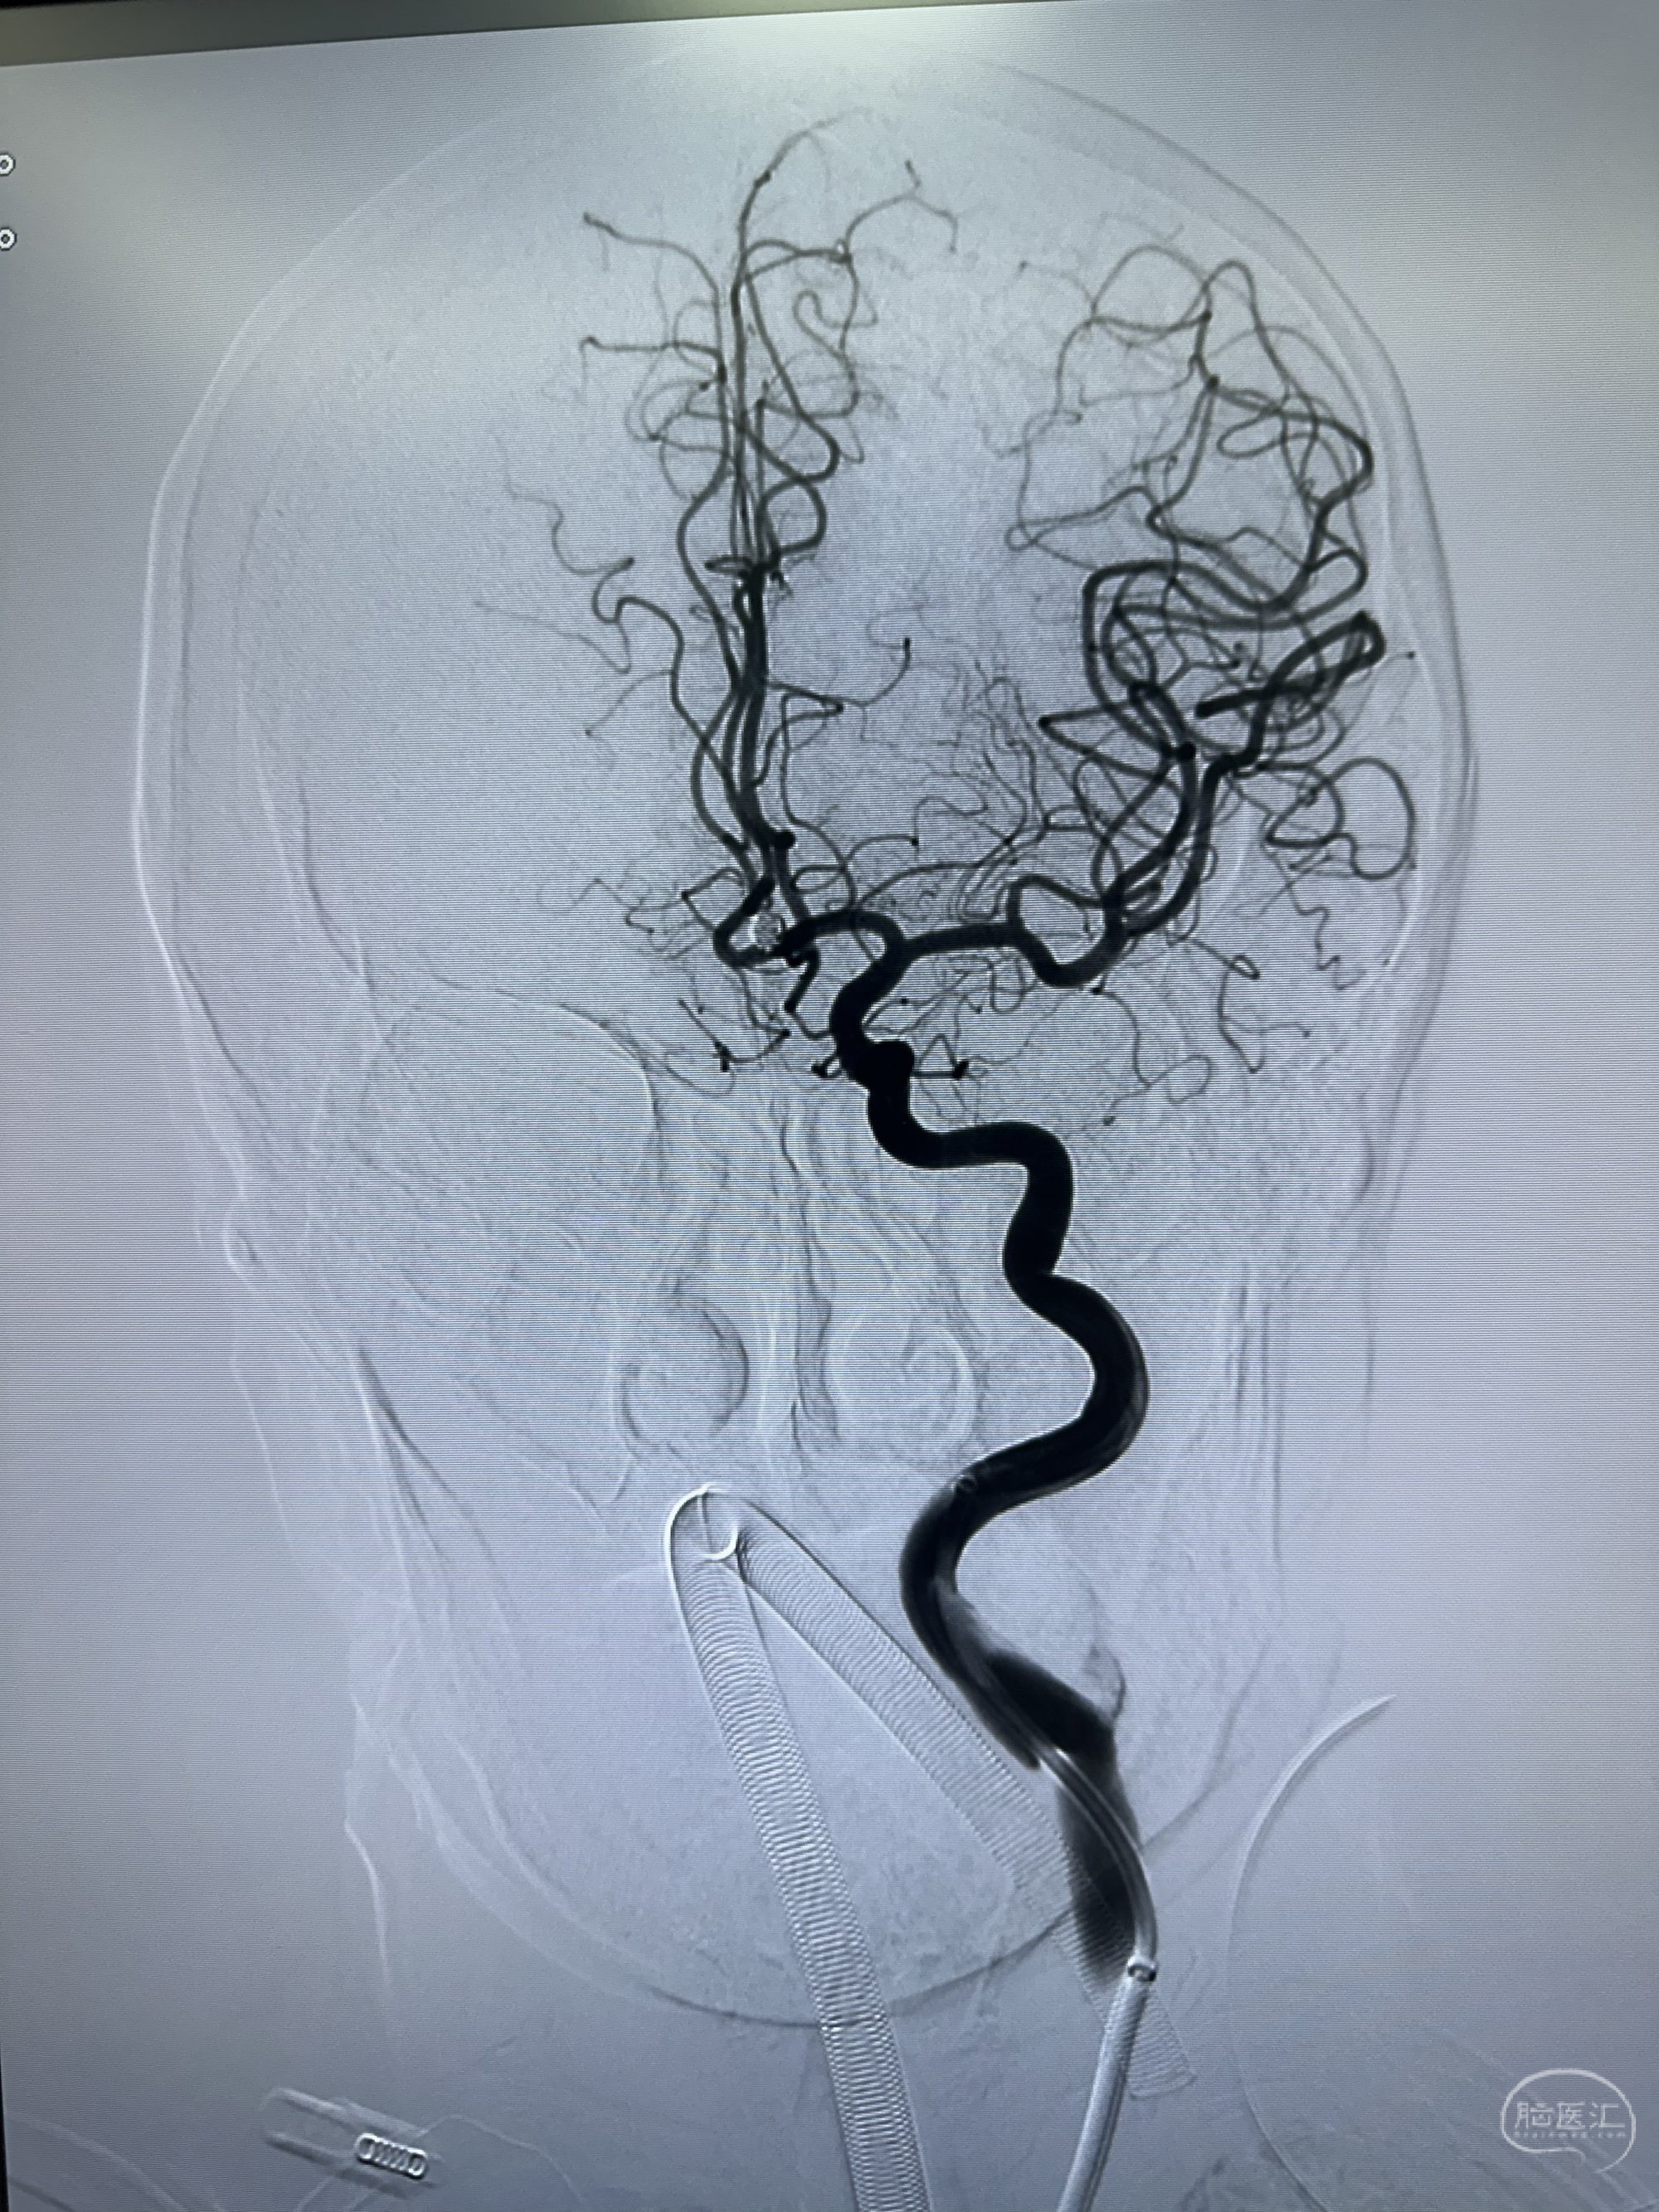

左侧造影

侧位

右侧颈内动脉造影

工作角度,选择Neuromax90加上6f的银蛇115